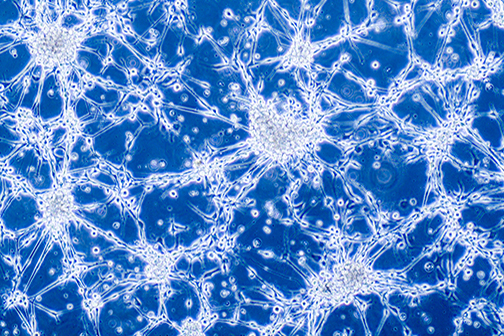

LSU Health New Orleans Develops New Human Cell Line to Study Blinding Eye Disorders

Under the direction of Boyd Professor Nicolas Bazan, MD, PhD, scientists at LSU Health New Orleans Neuroscience Center of Excellence have developed a new, experimental human cell line from retinal pigment epithelial cells. Called ABC, these cells so closely resemble and retain the properties of native retinal pigment epithelial (RPE) cells, the research team has shown that they are a reliable cell system to study retinal degenerative diseases. More